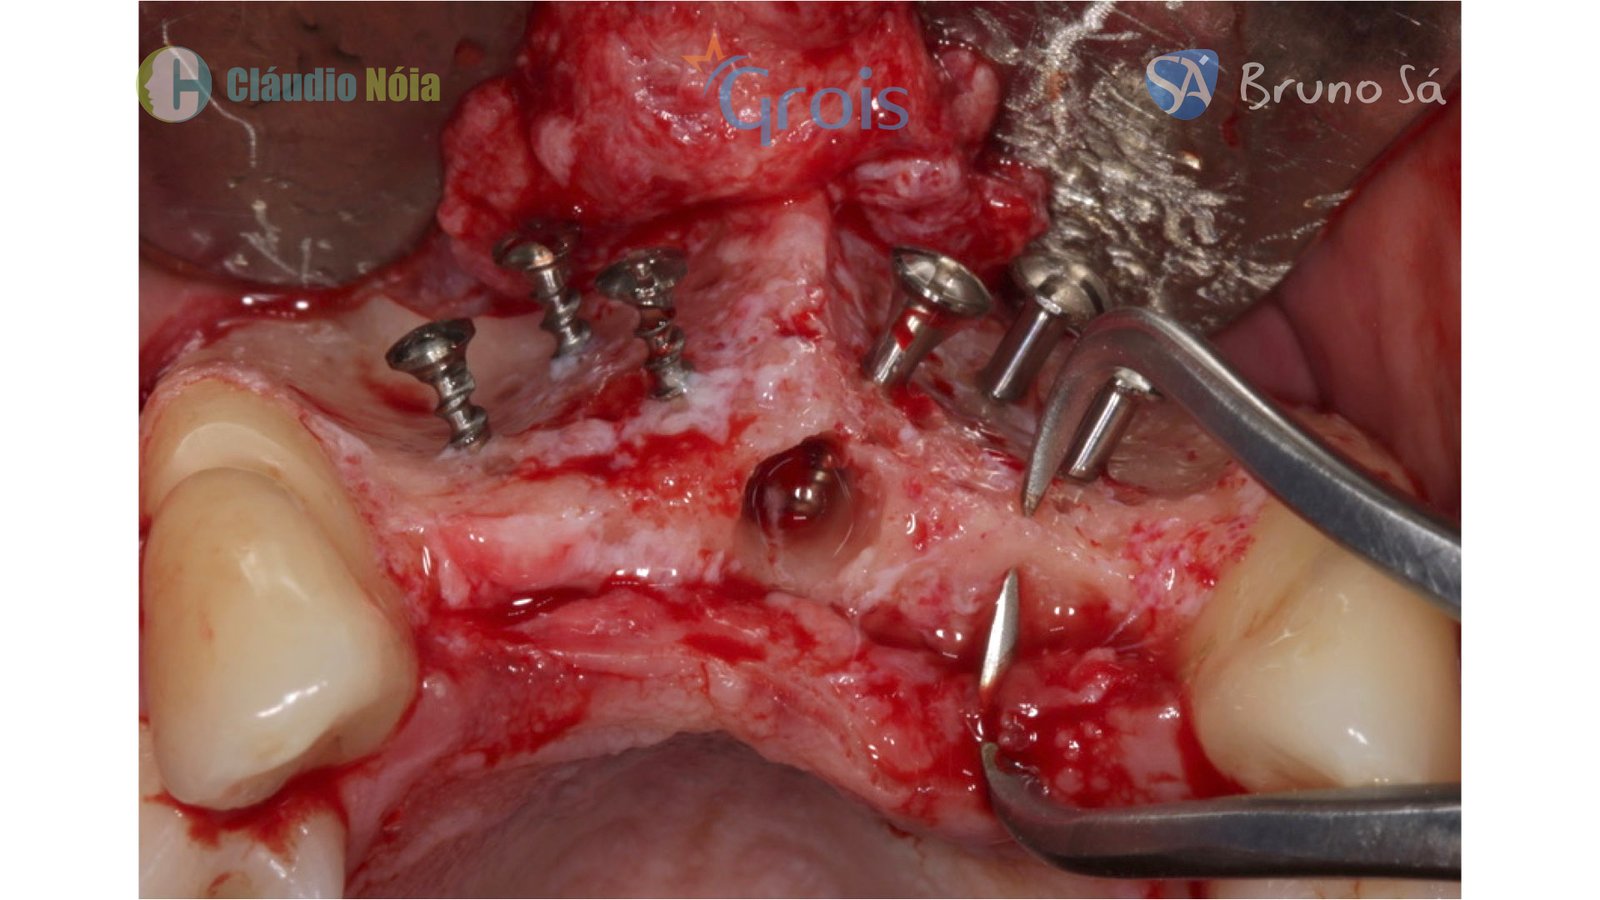

Para realização da técnica Screw Tent Pole são utilizados parafusos que funcionam como tenda para suportar o tecido mole, bem como são utilizados biomateriais e membrana de colágeno (ou Fibrina Rica em Plaquetas-PRF) visando promover a neoformação óssea.

Paciente apresentou-se a Área de CBMF da Instituição com a pré-maxila edêntula (Figuras 1, 2 e 3) e foi submetido a técnica Screw Tent Pole utilizando os parafusos da linha Orth – Implacil de Bortolli (Figura 3). Do lado direito da pré-maxila foram instalados 3 parafusos que apresentavam roscas em toda superfície, enquanto que do lado esquerdo foram instalados 3 parafusos que não apresentam roscas no terço cervical (Figuras 4, 5, 6, 7 e 8). Biomaterial associado com PRF (Stick Bone) foi adequadamente acomodado na região e recoberto por membranas de PRF (Figuras 9, 10 e 11). Uma sutura livre de tensão foi realizada para finalizar o procedimento cirúrgico (Figuras 12 e 13).